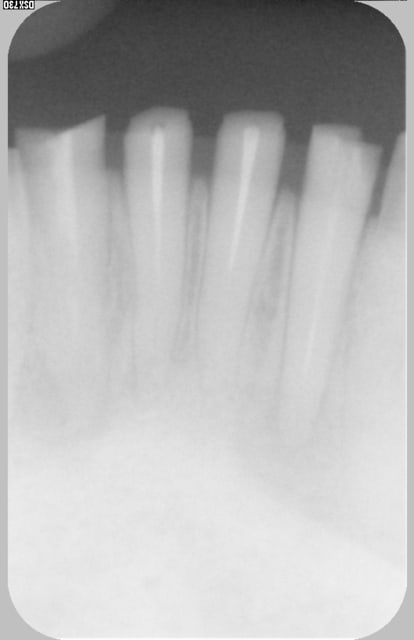

Les 4 incisives mandibulaires, sont nécrosées.

oublié rd initial des inc md (cones resine)

Initial rd w9tduk - Eugenol